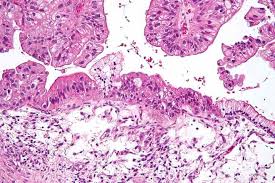

Diagnosis Of Ovarian Cancer The Bmj from www.bmj.com The main risk factor for ovarian cancer is getting older. I have posted on here many times, i too have advanced ovarian cancer, stage 4. If your doctor is concerned that you have ovarian cancer, they'll likely recommend a pelvic exam. The only way to confirm a diagnosis of ovarian cancer is by taking a tissue sample (biopsy) and looking at the cells under a microscope. It is most commonly diagnosed in women who are over 50 years of age. Most common type of ovarian cancer (about 9. In rare cases, a suspected ovarian cancer may be biopsied during a laparoscopy procedure or with a needle placed directly into the tumor through the skin of the abdomen. Ovarian cancer can be difficult to diagnose at an early stage, largely because symptoms can be vague and similar to those of other common illnesses.